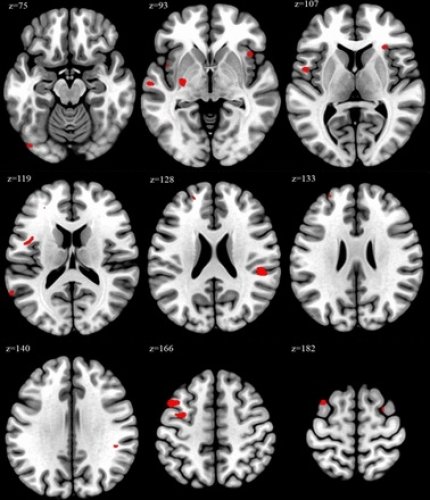

Ученые использовали технику нейровизуализации для анализа объема мозга исследуемых медработников. Это позволило определить и сравнить различия в уровнях серого вещества на разных участках мозга.

У людей, работавших 52 или более часов в неделю, наблюдались значительные изменения в участках мозга, связанных с когнитивной функцией и эмоциональной регуляцией, в отличие от участников, работавших по стандартным часам.

Участки мозга, где было зафиксировано увеличение объема, включают среднюю лобную извилин, играющую ключевую роль в когнитивных функциях, внимании, памяти и речевых процессах, а также долю, вовлеченную в эмоциональную обработку, самосознание и понимание социального контекста.

Исследователи считают, что выводы свидетельствуют о «потенциальной связи» между увеличением рабочей нагрузки и изменениями в этих частях мозга.